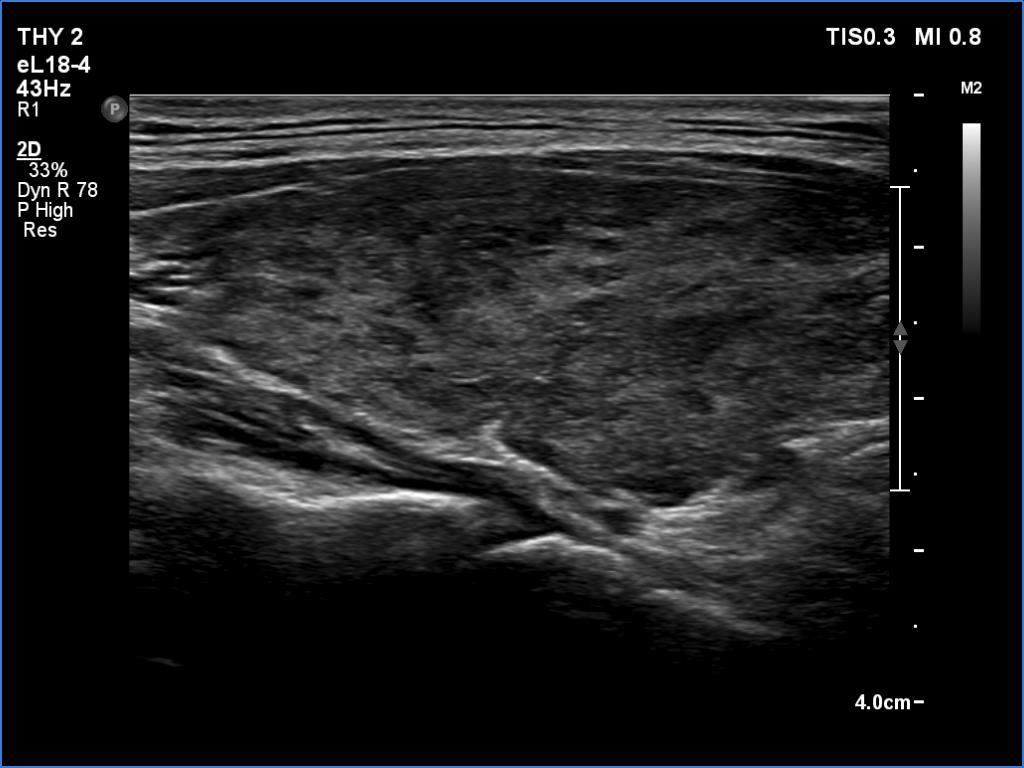

Left lobe, transverse scan

Clinical data: A 35-year-old woman was referred for a newly diagnosed hyperthyroidism. The patient had typical complaints, including elevated heart rate and weight loss.

Comment.

This is the typical course of a non-relapsing Graves' hyperthyroidism. As the hormone results improve, both the size of the initially enlarged goiter and the degree of hypoechogenicity decrease.